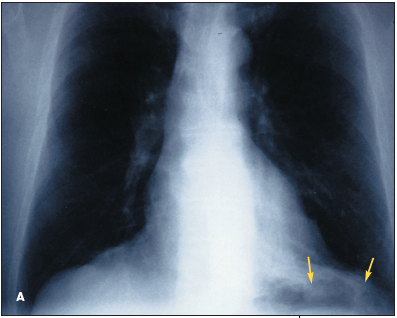

Systemic to pulmonary arteriovenous fistulas are extremely rare.